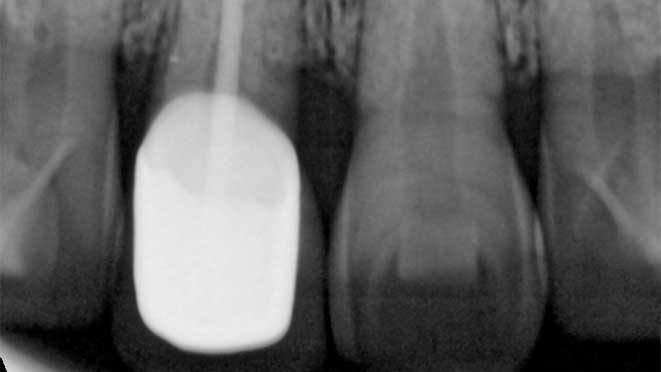

All on 4 dental implants are a type of dental restoration that provides a permanent alternative to traditional dentures and bridges. Unlike other options, All on 4 implants require only four arches of dental implants, which can be implanted at an angle in cases of minimal bone height. This innovative technique provides maximum support and allows for a complete set of teeth with minimal implants.

Finally, in most cases, All on 4 dental implants do not require bone grafting, which can be a significant advantage for individuals with minimal bone height or other considerations that might make traditional implant procedures difficult or impossible. This eliminates the need for a bone grafting before implant surgery.

Minimal bone height can also be considered, as All on 4 implants can be implanted at an angle to maximize the use of existing bone. However, it is essential to consult with a dental professional to determine the best restorative option for each individual's unique needs and concerns.